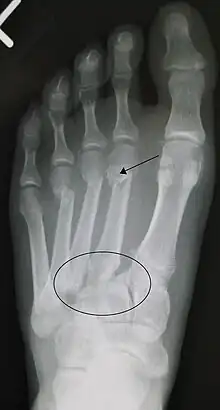

Lisfranc fracture (marked by the oval). This case also has fractures of the distal second (marked by the arrow), third, and fourth metatarsal bones.

In a high energy injury to the midfoot, such as a fall from a height or a motor vehicle accident, the diagnosis of a Lisfranc injury should, in theory at least, pose less of a challenge. There will be deformity of the midfoot and X-ray abnormalities should be obvious. Further, the nature of the injury will create heightened clinical suspicion and there may even be disruption of the overlying skin and compromise of the blood supply. Typical X-ray findings would include a gap between the base of the first and second toes.[8] The diagnosis becomes more challenging in the case of low energy incidents, such as might occur with a twisting injury on the racquetball court, or when an American Football lineman is forced back upon a foot that is already in a fully plantar flexed position. Then, there may only be complaint of inability to bear weight and some mild swelling of the forefoot or midfoot. Bruising of the arch has been described as diagnostic in these circumstances but may well be absent.[9] Typically, conventional radiography of the foot is utilized with standard non-weight bearing views, supplemented by weight bearing views which may demonstrate widening of the interval between the first and second toes, if the initial views fail to show abnormality. Unfortunately, radiographs in such circumstances have a sensitivity of 50% when non-weight bearing and 85% when weight bearing, meaning that they will appear normal in 15% of cases where a Lisfranc injury actually exists.[10] In the case of apparently normal x-rays, if clinical suspicion remains, advanced imaging such as magnetic resonance imaging (MRI) or computed tomography (CT scan) is a logical next step.[11]